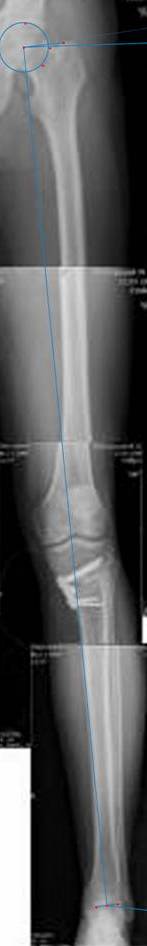

картинки оперированного пациента 40 лет, травма в 2006 году.

оперирован 06.11.2009г - корригирующая остеотомия большеберцовой кости.

Я картинку собрал с некоторыми погрешностями, если провести отвес от центра вращения головки бедра до середины голени (на пациенте),то имеется небольшой вальгус (гиперкоррекция)конечно она (гиперкоррекция) не достигает 10 гр, но 5 гр она достигает.

Проблема как сделать рентгеновские снимки а потом их совместить правильно, кто знает как решить этот вопрос. Ведь стандартные размеры рентгенкассет, оснащенные наши стационары отснять всю конечность с трех попыток!

Уважаемый д-р Батал Шушания,

К сожалению, не очень удачный пример. Если верить Р-граммам, имеет место быть дисплазия мыщелков бедренной кости с наклоном суставной линии. Это уже создает сложности получения хороших отдаленных результатов. Кроме того, по классике, необходима гиперкоррекция с созданием вальгуса 7-10 градусов для максимальной разгрузки медиального отдела КС. Если верить укладке, то линия сустава имеет четкий варусный наклон, поэтому результат операции м.б. кратковременным. В этих случаях показана двойная остеотомия бедра и тибии.

Если сделать правильно, то видно, что бедренная кость в порядке, а цель остеотомии (низкой, кстати), не достигнута вовсе.

Сохраняется варус. Для того, чтобы создать вальгусную гиперкоррекцию, не моделируя при этом откровенный Х голени, можно сделать медиализирующую остеотомию.